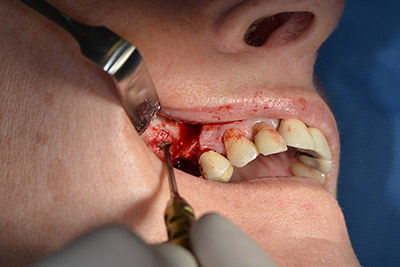

Las perforaciones siguientes se realizan a una velocidad reducida de 300 rpm. Y es aquí donde se demuestra una de las ventajas de Implantmed. El protocolo quirúrgico puede predefinirse y las diferentes posiciones pueden seleccionarse pisando el pedal hacia la posición "P" (figuras 10 a 11).

La siguiente posición programada es ya la incorporación del implante que, en nuestra práctica, se preconfigura a una fuerza de 32 Ncm (figura 12).